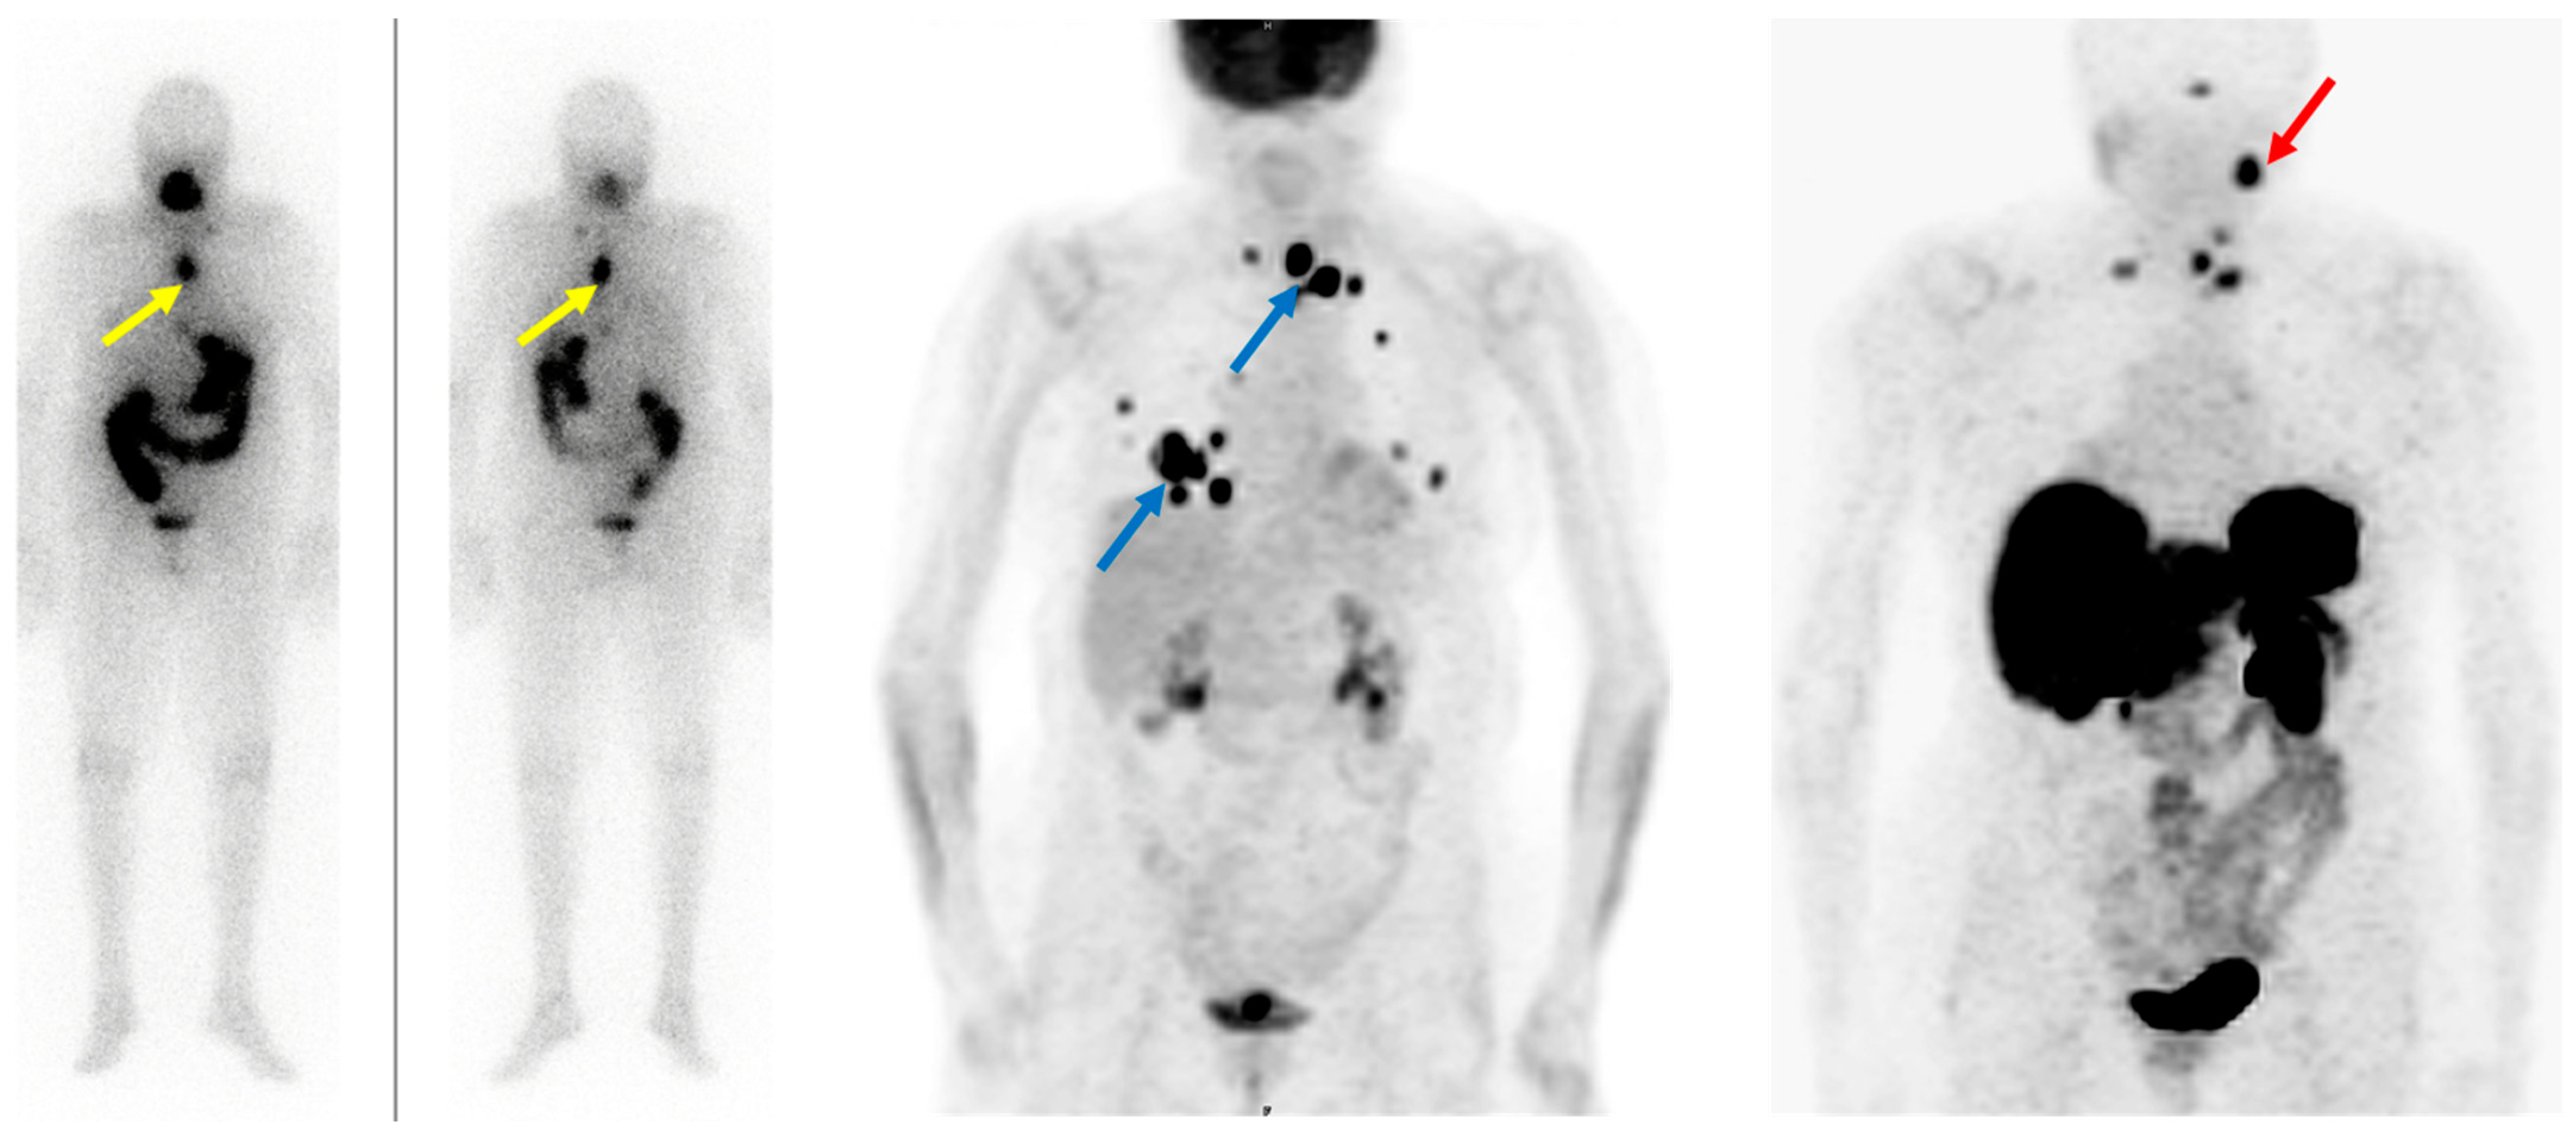

- De Vries, L.H.; Lodewijk, L.; Braat, A.J.A.T.; Krijger, G.C.; Valk, G.D.; Lam, M.G.E.H.; Borel Rinkes, I.H.M.; Vriens, M.R.; de Keizer, B. 68Ga-PSMA PET/CT in Radioactive Iodine-Refractory Differentiated Thyroid Cancer and First Treatment Results with 177Lu-PSMA-617. EJNMMI Res. 2020, 10, 18. [Google Scholar] [CrossRef] [PubMed]

- Rizzo, A.; Racca, M.; Dall’Armellina, S.; Delgado Bolton, R.C.; Albano, D.; Dondi, F.; Bertagna, F.; Annunziata, S.; Treglia, G. Potential Role of PSMA-Targeted PET in Thyroid Malignant Disease: A Systematic Review. Diagnostics 2023, 13, 564. [Google Scholar] [CrossRef]